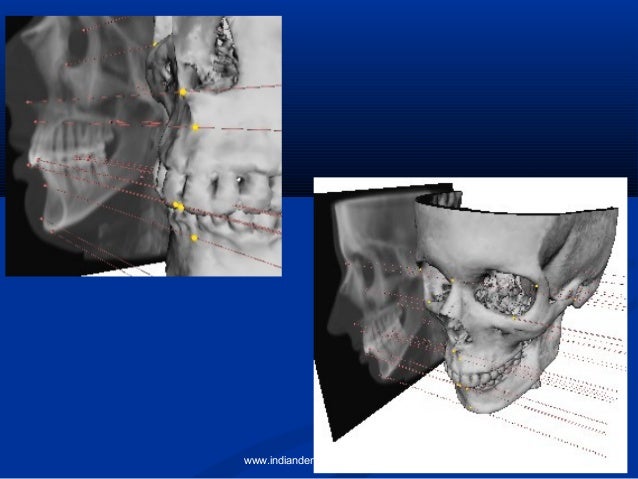

We are a proud partner of For Your Imaging Technologies, Inc. makers of the Dr. Ceph and Dr. View software programs. Dr. Ceph, a cephalometric analysis program with image morphing, was the first of its kind to superimpose the x-ray and photograph into one manipulable image which shows both hard and soft tissue. Offering cervical vertebrae, frontal, lateral, and occlusal analyses, image morphing, and the newest ABO superimpositions. Dr. Ceph offers the powerful features required to process your analysis quickly and accurately, every time. Ask us about customizing an analysis specifically for your practice!